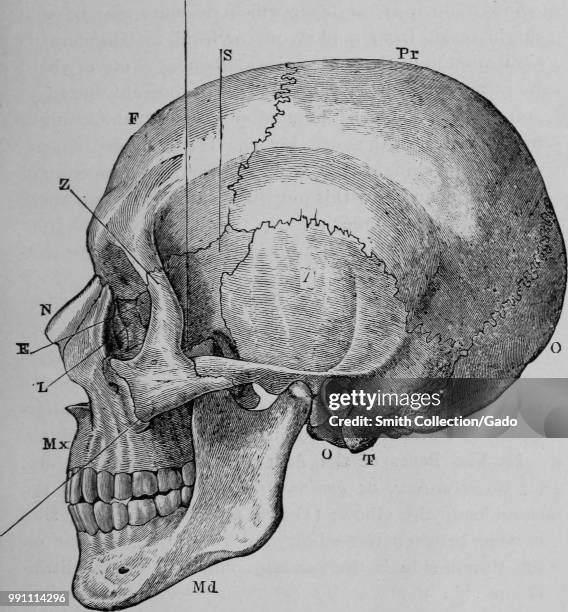

Prepare to be captivated by List, a showcase of real human skull front view black and white imagery powered by ieltschampions.edu.vn. More related visuals are below.

real human skull front view black and white

Posts: real human skull front view black and white